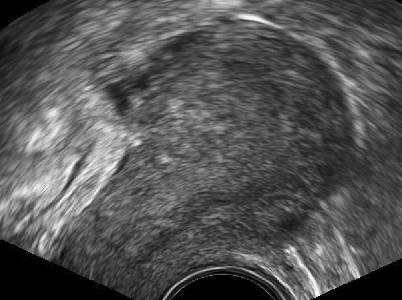

Abb. 3

Zystische Strukturen im Myometrium, die einzeln oder in Gruppen vorkommen können, finden sich bei Adenomyose